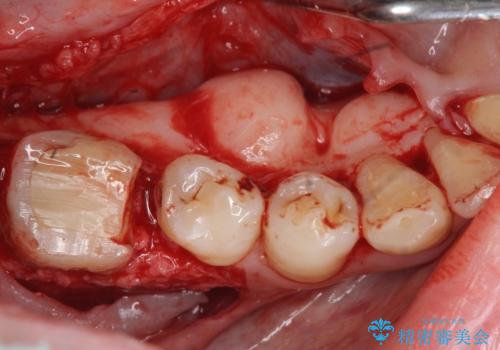

奥歯は既に根管治療が為されクラウンを装着する必要性がある状態ですが、歯の高さが低くクラウンの安定性・強度を担保するために歯周外科を行う治療計画としました。

歯周外科を行うことで、歯ぐきの位置を下げ歯の高さを作り出し安定したクラウンの装着が可能となります。また同時に舌の邪魔となっていた骨隆起の除去を行うこととしました。

歯周外科に際しては、静脈内麻酔を行うことでほとんど記憶のないうちにリラックスした状態で受けていただくことができました。